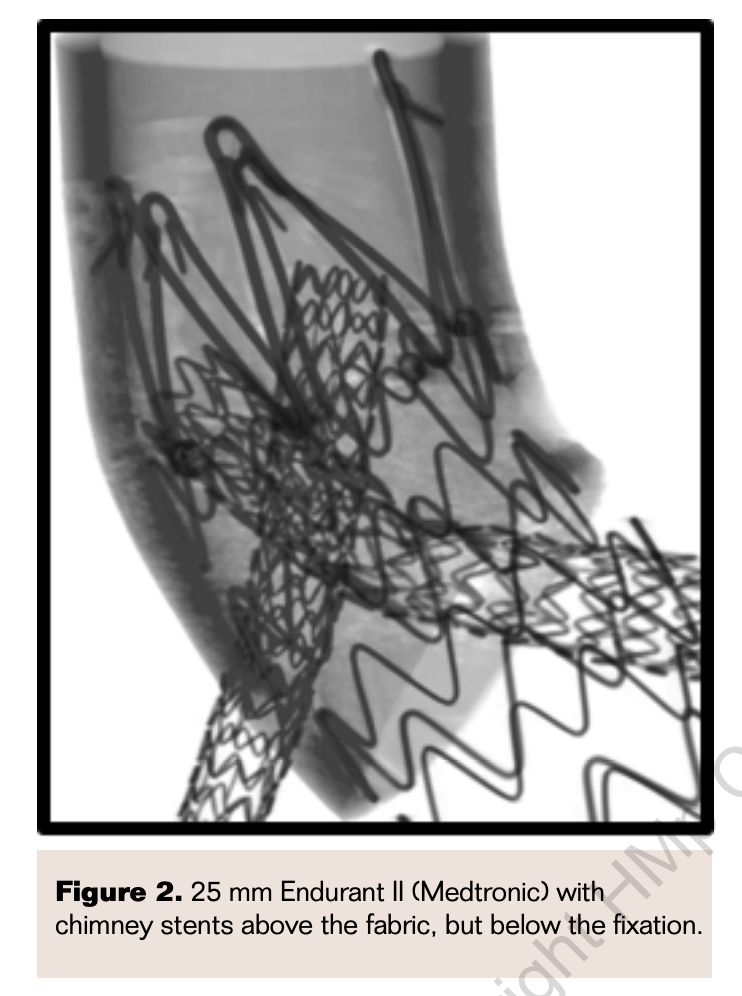

The chEVAR technique used by our group, as well as others, involves a minimum of 2 access point: femoral and an upper extremity.4,6-8,13 Femoral access can be completed in a percutaneous fashion. One or both upper extremities are accessed dependent on the number of chimney grafts planned. We utilize an open approach to the axillary artery and most commonly use the right side due to ease of positioning and access by the surgeon. We gain proximal and distal control of the axillary artery and place a 10 mm Dacron conduit. This conduit serves as the access point for the sheaths and wires during chimney graft placement (Figure 1). Each 7 Fr sheath placed in the conduit is labeled with the vessel it is selectively catheterizing. Once the selected branches have wires in place, the aortic endograft is deployed and subsequently, each chimney graft is deployed with a planned 15 mm to 20 mm overlap with the aortic endograft and extending 10 mm to 15 mm beyond the proximal extent of fabric of the aortic endograft. An effort is made to place the chimney graft below the “suprarenal” or active fixation of the device.

The potential advantage of the chEVAR technique using devices designed with suprarenal fixation is that it separates the potentially compromised fixation and seal that occur using this technique. The chimney stents can be specifically placed above the fabric of the device, but below the fixation, so that fixation is not compromised (Figures 2 and 3). This technical aspect still allows for potential “gutter” endoleaks, but will likely minimize the risk of migration. Micro and standard computed tomography (CT) scan imaging have demonstrated the successful interaction between the chimney stents and an endograft with suprarenal fixation (Figures 4 and 5). The above data from the registries and micro and standard CT scan imaging confirm the efficacy of this technique with suprarenal fixation.